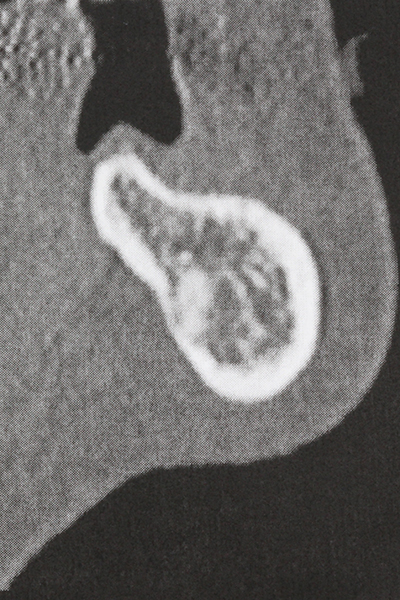

As shown in the past, basically any bone surgery procedure represents a possible indication for piezosurgery. Thus preparation of the mobile segment in distraction osteogenesis (Fig. 23-25) and sandwich osteotomy uses special attachments without endangering the blood supply to the crestal section, which is essential for the success of both techniques (Gonzalez-Garcia, Diniz-Freitas et al. 2008).

Purely orthodontic indications include orthognathic surgery, genioplasty (Fig. 27-30) and orbital decompression in patients with advanced endocrine orbitopathy as a result of Basedow’s disease (Ponto, Zwiener et al. 2014). Piezo devices are also used in maxillofacial surgery and to remove tumours at the base of the skull in various hospitals.